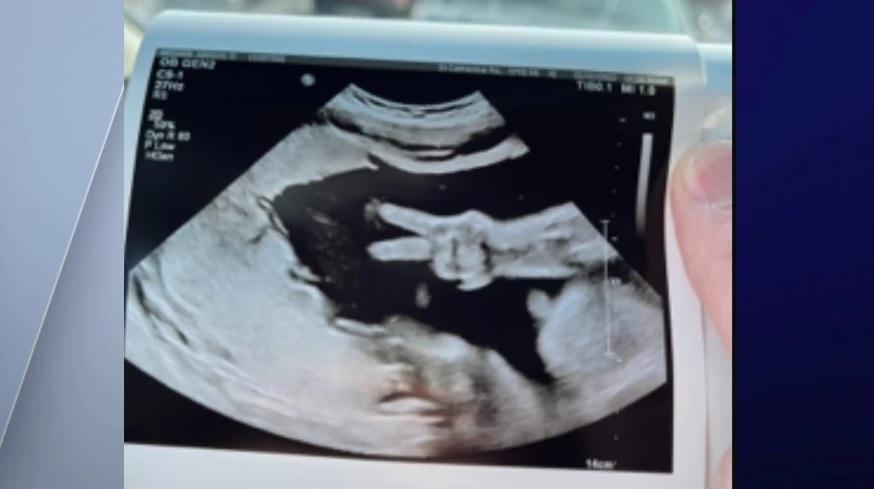

休斯敦在Twitter貼出B女的反叛超聲波照。(互聯網)

英國倫弗魯郡(Renfrew)的21歲準媽媽休斯敦(Jemma Houston),肚裡的女兒還未出世就給她帶來驚喜。休斯敦上周二接受超聲波產檢時,「驚見」腹中的B女竟擺出不禮貌的反V手勢,正正遮住小蛋面,休斯敦看了後哭笑不得,也輕輕抱怨本周末要再照一次,因為每次都無法看到B女的真面目。

休斯敦把B女的「反叛」超聲波照放上Twitter,笑言女兒是「英國最沒禮貌的嬰兒」,又說「女兒每次都不合作,因此我不得不再做掃描」,「那麼,周六再來吧,這次請記得露面,媽媽是真心的」。網民看後紛紛表示,「這真可愛」。